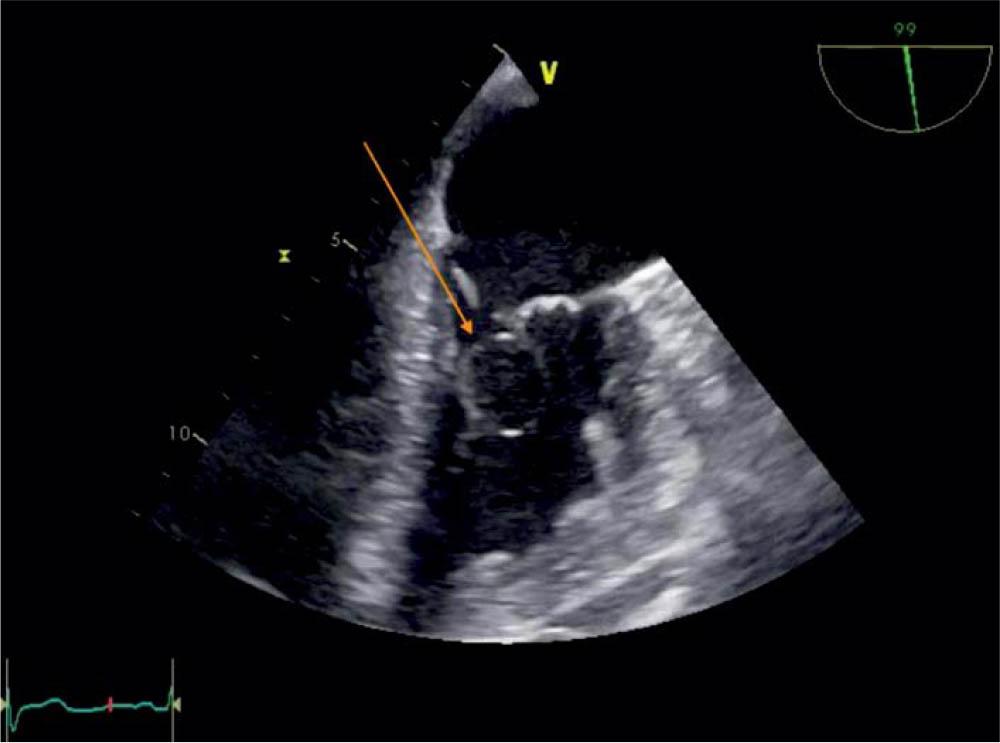

Figure 3